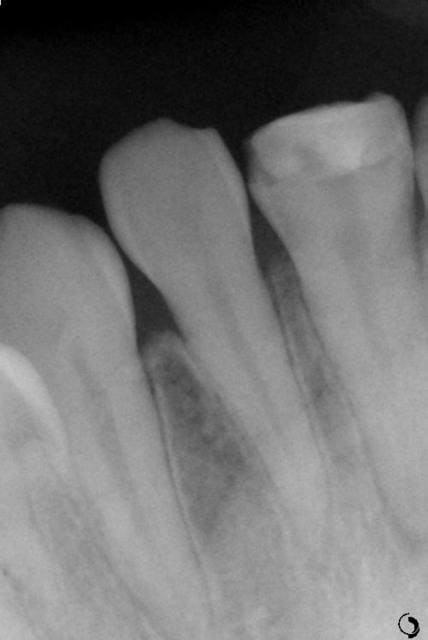

Une semaine plus tard, il arrive à mon cabinet avec une lettre du service dentaire et voilà son état:

- 12, 11 et 21 sont très mobiles et avec des contacts en occlusion

- test au froid positif sur les 4 incisives

J'ai réalisé la bio de la 21 et je voulais avoir votre avis sur la contention, les dents sont très mobiles, et sur les radios j'ai l'impression qu'elles sont sorties de leurs alvéoles. Qu'est ce que vous me conseillez?

je ne pense pas qu'elles soient sorties de leurs alvéoles, mais c'est plutôt le ligament qui est élargi du fait de l'inflammation causée par le traumatisme.